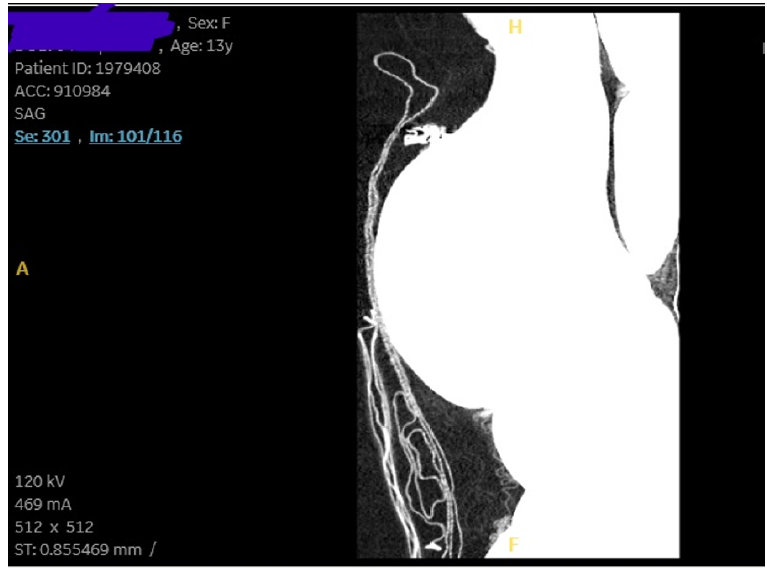

Giant Hemorrhagic Ovarian Cyst in an Adolescence Girl; A Case Report

Azka Mujeeb and Shalini Malhotra. 12(1): 61-67.